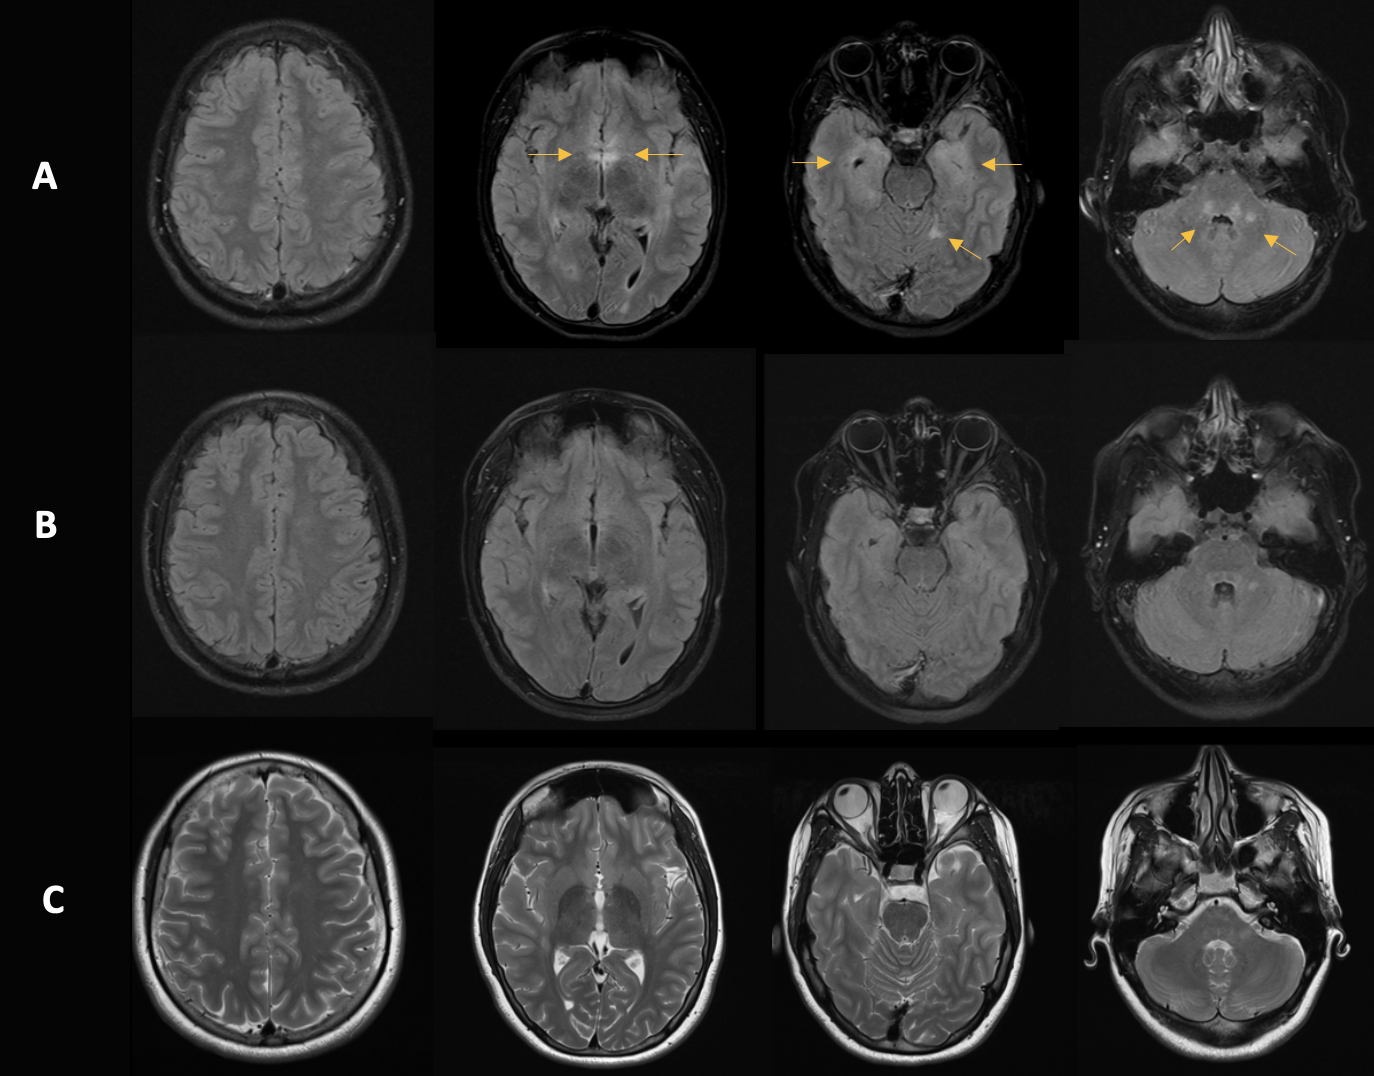

Figura 2: Follow-up mediante risonanza magnetica. A: Imaging iniziale. B: Follow-up dopo 10 mesi. C: Follow-up dopo due anni. Si osserva una chiara riduzione delle iperintensità T2w nel tempo, che si correla con il miglioramento clinico.